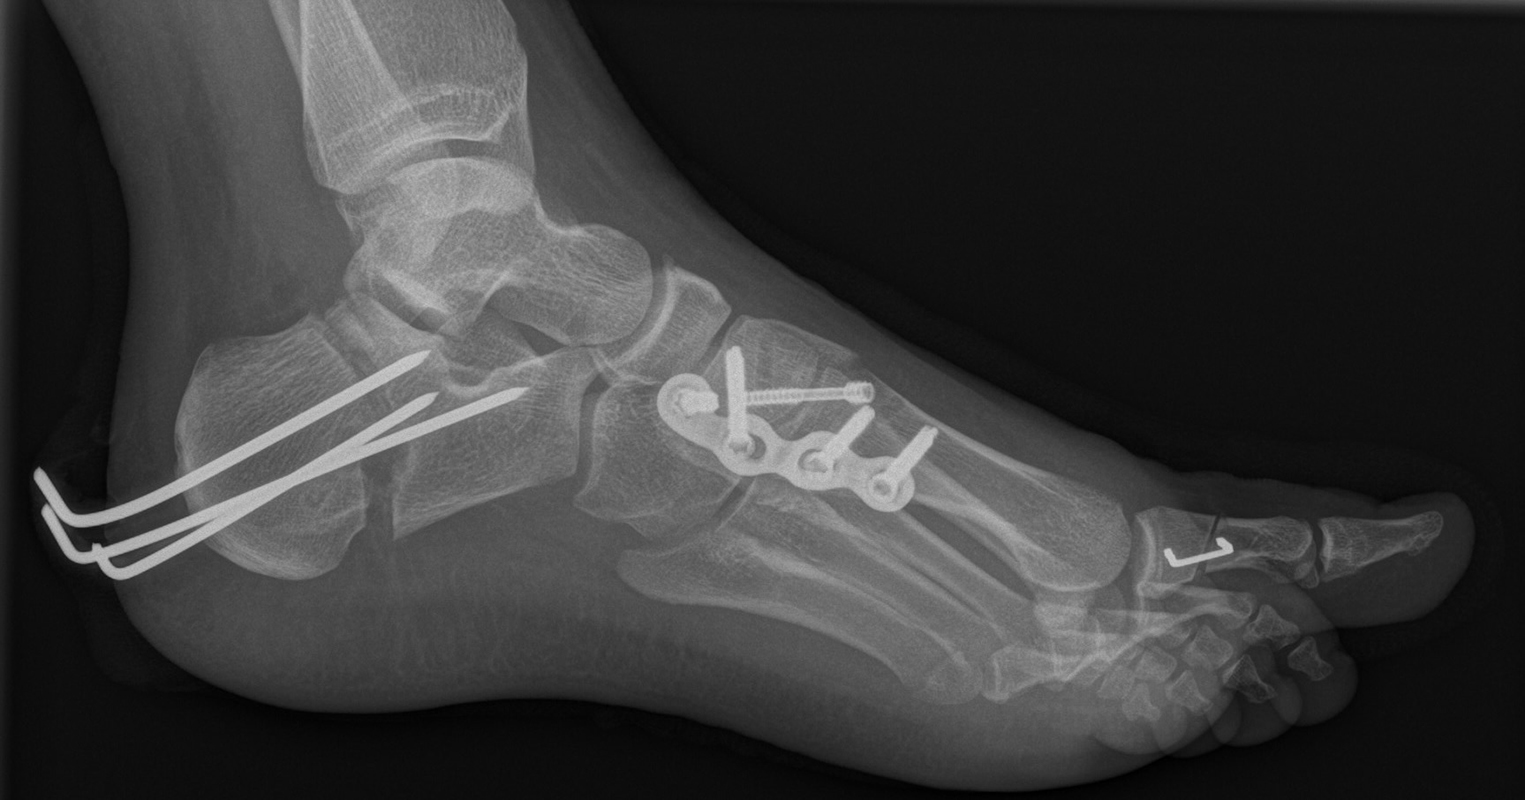

Knick-Senk-Platt-Fuß Korrektur mit dem Canalis Tarsi Spacer

In der Korrektur des schmerzhaften, aber flexiblen Knick-Senk-Fußes oder Plattfußes ist die Schraubenarthrorise mit einem Sinus tarsi oder besser bezeichnet als Canalis tarsi Spacer und alternativ mit einer Calcaneus-Stopp-Schraube seit vielen Jahren ein etabliertes Verfahren und führt zu einer kompletten Korrektur von flexiblen Knick- und Plattfuß-Fehlstellungen (Abb. 7). Die nötige Schnittlänge über dem Sinus tarsi beträgt für beide Verfahren 1 cm.

Abb. 7 a-e: Knick-Senk-Fuß prä- und postoperative Situation (a-b), ventrale und dorsale Ansicht (c-d). Laterale Ansicht des Hautschnittes über dem Sinus tarsi (e).

Zum Lesen der Bildbeschreibung und zur Vollansicht bitte die Bilder anklicken. Bilder: A. Helmers.